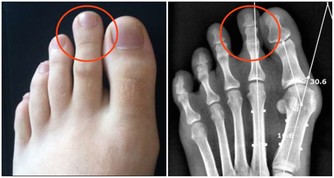

嚴重的就會出現下肢動脈硬化閉塞症,

也就是下肢動脈粥樣硬化斑塊造成的病症,這種病症在早期就有腿腳抽筋的症狀。